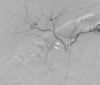

6

Q

A

appendix